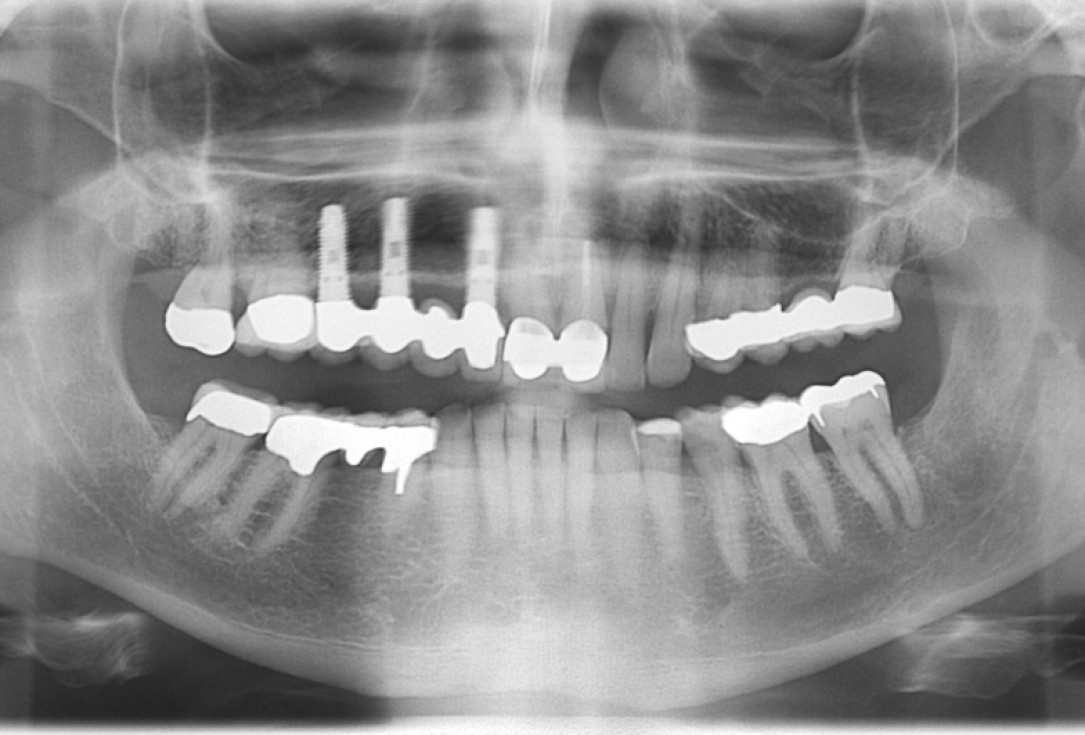

botiss cerabone® & Jason® membrane for horizontal augmentation - Clinical case by Dr. M. Steigmann

Three implants placed in a narrow posterior mandible